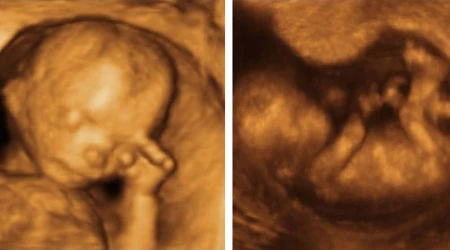

Pese a las pocas probabilidades el bebé sobrevivió a la cirugía de cuatro horas, y a las 16 semanas empezó con las quimioterapias. El niño nació en la semana 36, fuerte y totalmente sano, nadie podía creer que ese pequeño hubiera vivido todo el proceso junto a su madre. Por ello, Viviana y su esposo decidieron llamarlo "Gabriel", que significa "la fuerza de Dios".